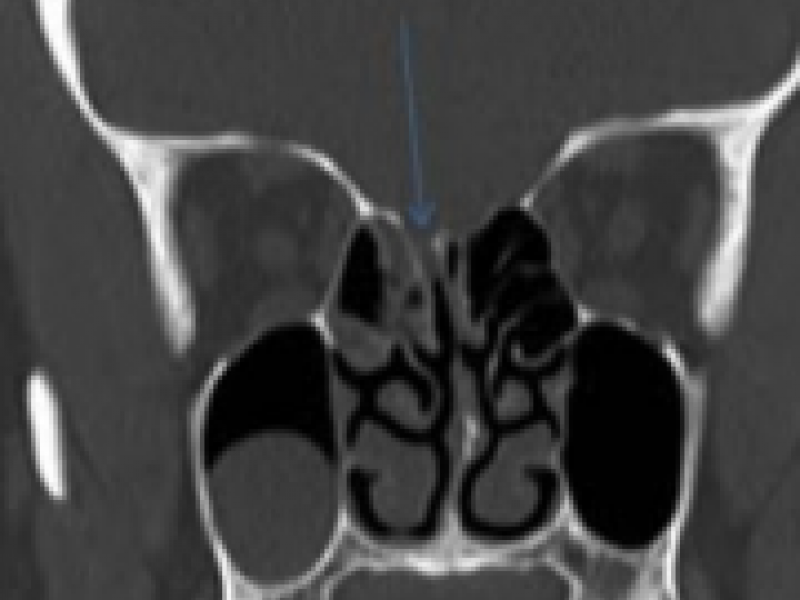

A young female comes in with persistent unilateral clear